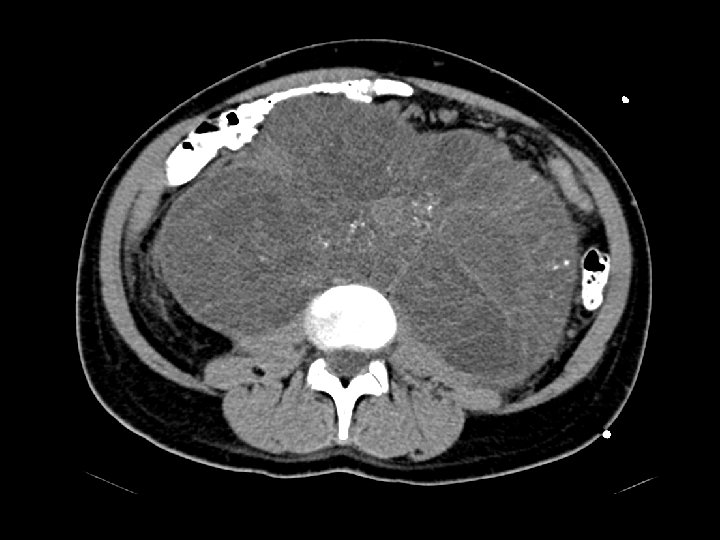

Metastatic germ cell tumor • Findings: – left neck soft tissue mass – pulmonary nodules – large retroperitoneal mass with speckled calcifications • ddx: – lymphoma